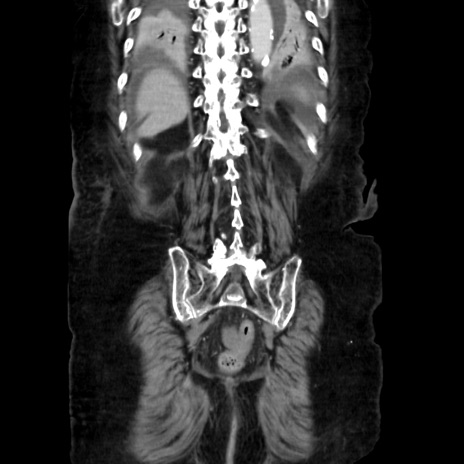

症例40(冠状断像)

【症例】90歳代女性

【主訴】腹痛・嘔吐

【現病歴】 食欲低下、嘔吐があり昨日他院受診。肺炎と診断され入院となる。入院後より腹部全体に圧痛あり。胃管留置され経過みていたが、症状持続するため、

当院転院となる。

【既往歴】胸椎圧迫骨折、胆石症

【身体所見】腹部:中央に激痛あり、圧痛あり、反跳痛不明

【データ】WBC 17100、CRP 18.82

矢状断像